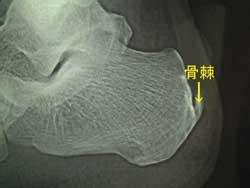

微创治疗骨刺怎么样?骨刺是一种很严重的骨科疾病,病发后患者会感觉全身酸痛,疼痛难忍,骨刺的产生让中老年人遭受了许多的困扰。在确诊骨刺后,一定要积极的进行治疗。而治疗骨刺的方法有很多,如保守治疗、手术治疗以及微创治疗等,那么,微创治疗骨刺怎么样?来看看。》》》点击此处,直接预约挂号

云南骨科医院专家介绍,微创治疗是目前治疗骨刺效果比较好的方法,因为微创治疗具有安全、微痛、治疗时间短、并发症少以及恢复快等等有点,因此受到许多患者和专家的推崇。